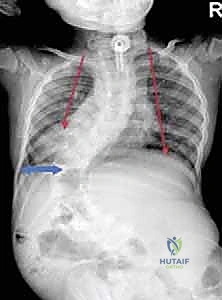

- الأشعة السينية (X-rays) البانورامية: يتم أخذ صور للعمود الفقري بالكامل من الأمام والخلف والجانب (أثناء وقوف الطفل أو جلوسه إذا كان لا يستطيع الوقوف). يتم من خلالها قياس "زاوية كوب" (Cobb Angle) لتحديد شدة الانحناء.

الفكرة العبقرية وراء قضبان النمو هي "التثبيت دون الدمج". يقوم الدكتور هطيف بتثبيت العمود الفقري من الأعلى (عند الفقرات الصدرية العليا) ومن الأسفل (عند الفقرات القطنية أو الحوض) باستخدام مسامير أو خطاطيف تيتانيوم. يتم توصيل هذه المثبتات بقضبان معدنية قوية تمتد عبر منطقة الجنف.

- تثبيت الدعامات: يتم إدخال مسامير التيتانيوم (Pedicle Screws) أو الخطاطيف بدقة متناهية تحت توجيه الأشعة السينية (Fluoroscopy) في الفقرات العلوية والسفلية.